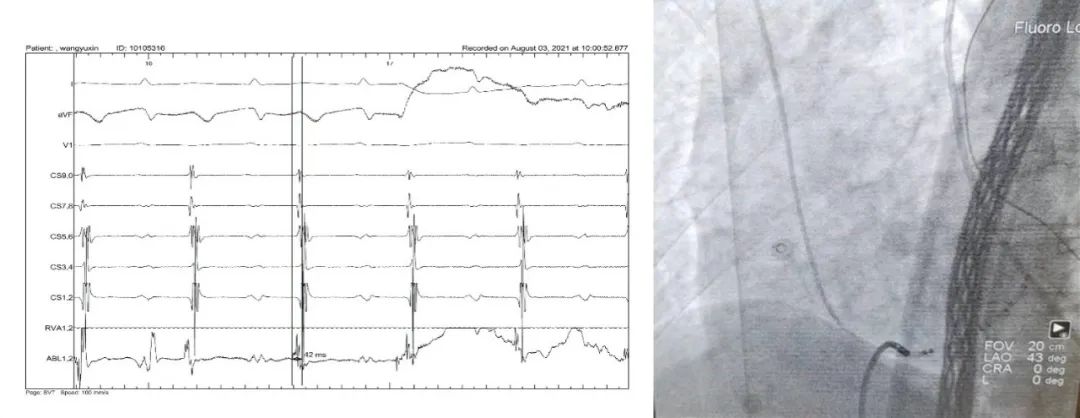

患者女性,74岁,汉族。主因“间断心悸2个月”入院。患者2个月前开始无明显诱因发作心悸,自测心率150-190bpm,持续约30min可缓解,外院心电图提示“心房扑动”(图1),给予口服倍他乐克治疗,效果不明显,为进一步诊治收入院。既往:20年前行甲状腺腺瘤切除术,3周前发现血脂异常。入院后行Holter检查记录到心动过速,考虑为心房扑动2:1传导(图2),超声心动未见异常。完善术前准备后,行电生理检查及射频消融,常规穿刺右侧颈内静脉、右股静脉,送入CS及RV电极,CS 程序刺激500/350ms可诱发心动过速, 但并非术前预想的房扑,此时房室比例为1:1关系,心动过速周长420ms(图3),不符合房扑的频率。因为房室为1:1关系,我们行心室Burst刺激除外了不典型房室结双径路和后间隔旁路,确定患者为房性心动过速。送入消融电极导管,在CARTO系统指导下,激动标测右心房,在CS口附近标测到最早心房激动部位(图4),设置30W盐水灌注消融,放电5秒左右心动过速终止(图5),重复之前诱发条件,心动过速不再诱发。随访半年,患者未再发作心动过速。

图4.冠状静脉窦口附近记录到EAA

图5.消融5s心动过速终止